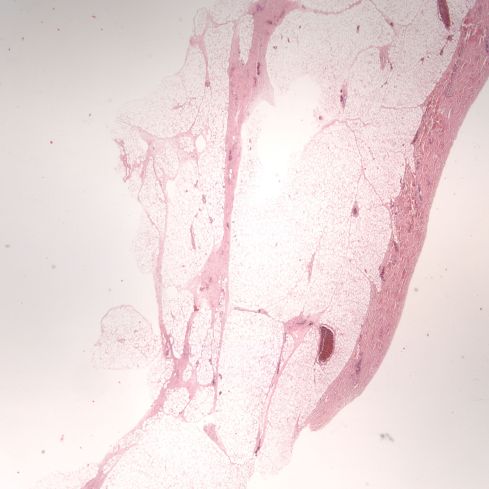

The gestational examination using the anatomic Ballard score was 33 weeks and that would place the autopsy body weight in the 75th percentile for this female infant. The heart was not disproportionately heavy. The pancreatic islets could not be histologically evaluated because of autolysis. The only evidence suggestive of maternal diabetes was the increased thickness of subcutaneous adipose tissue for gestation (Figure 1).

Figure 1: This low power photomicrograph of the skin is taken from the chest at the nipple level, the usual section location in the autopsy protocol. The deep layer of subcutaneous adipose tissue is abnormal at this gestation. (2x H&E)